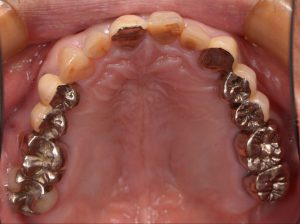

奥歯の銀歯が目立って気になる事を主訴に来院された患者様です。

初診時の写真です。

昔治療した際に保険診療を選択し、銀歯を入れたものの目立つのがずっと気になっていたとの事です。

奥歯はブリッジになっているため、現在の治療でも保険診療では同じような銀歯になってしまう事、金属の変形や摩耗などによる虫歯のリスクなどを説明しました。